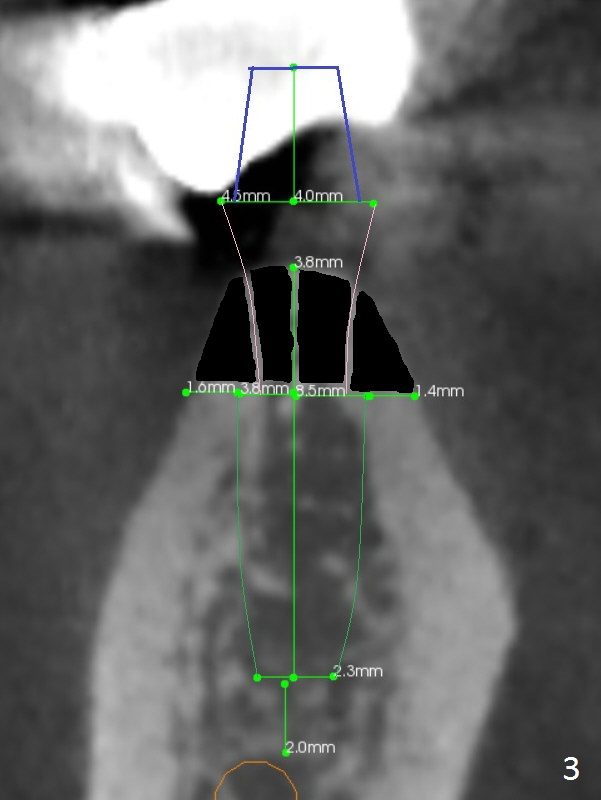

The ridge at #30 is pointed (Fig.2) and going to be resected (Fig.3 black area) to receive a narrow, short implant (3.8x8.5 mm).   A splinted immediate provisional will be fabricated following placement of a 4.5x4(5) mm abutment at #30 (Fig.2,3).  Take Alginate impression when the patient arrives in case the tooth #31 is also non-salvageable.